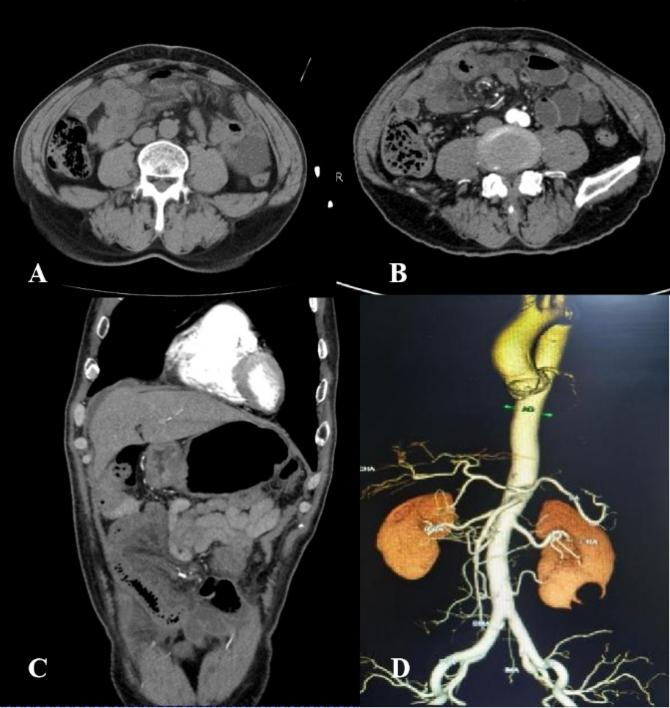

放射科迅速启动应急机制,第一时间为患者进行了腹部CT平扫。诊断团队快速、精准地判读了影像,由李一凡住院医师、常泰副主任医师首先发现患者小肠肠壁弥漫增厚、水肿,肠系膜多发渗出性改变(图1A),建议进一步行胸腹主动脉CT血管造影(CTA)检查以明确肠道血运情况。然后由温晨住院医师、张亚男副主任医师通过CTA表现(图1B-D)提示患者为回肠缺血性改变,不除外腹内疝可能,同时排除了腹主动脉夹层、肠系膜动脉血栓等急腹症,随即上报了危急值,并建议肿瘤外科/普外科积极干预。经普肿瘤外科/普外科叶晋生副主任医师与放射科霍健伟、李俊秋主任医师会诊后,患者最终确诊为肠系膜扭转伴不完全性小肠梗阻。

图1 A-D

图A,腹部CT平扫示右下腹回肠肠壁弥漫增厚、水肿,肠系膜片絮状渗出性改变。图B-C,腹部CT增强轴位及冠状面重建像显示回肠肠壁强化明显减弱,右下腹部为著,局部可见肠系膜血管扭转,另左侧小肠多发积液。图D,腹主动脉CTA的VR像显示腹主动脉及其较大分支未见明显异常。